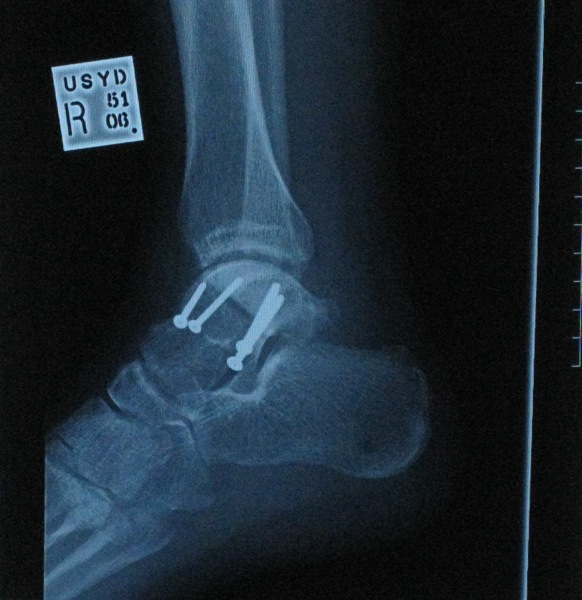

Took some more Xrays of the leg last week.

Lets just say that somebody was trigger happy on the old electric screwdriver :roll:

Ankle will be in a cast for another 5 weeks and then we'll see how i go. (Rehab-Physio etc )

IMG_0100.JPG

IMG_0100.JPG (96.33 KiB) Viewed 1543 times

damn dude! that looks more like a mechano set than an ankle! Hope it all heals up pretty well.